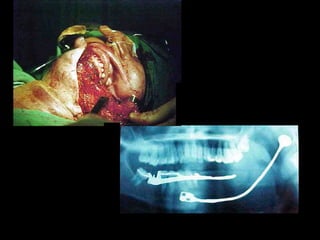

24 horas de postoperatorio

24 horas depostoperatorio

Penetración al compartimiento condilar, aquí se

Observa el muñón del cuello del cóndilo

Condilectomía

Prótesis total de cóndilo, debe cuidarse la relación oclusal.

Penetración al compartimientocondilar, aquí se Observa el muñón del cuello del cóndilo

Prótesis total decóndilo, debe cuidarse la relación oclusal.